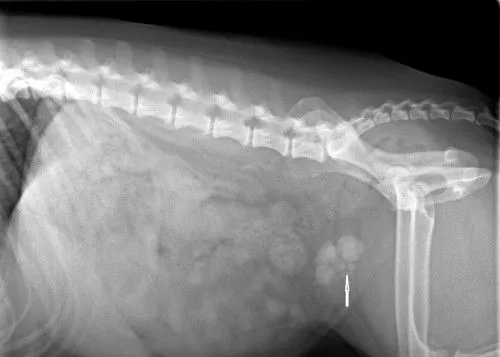

Bladder stones prior to surgery

Before Surgery (arrow shows stones)